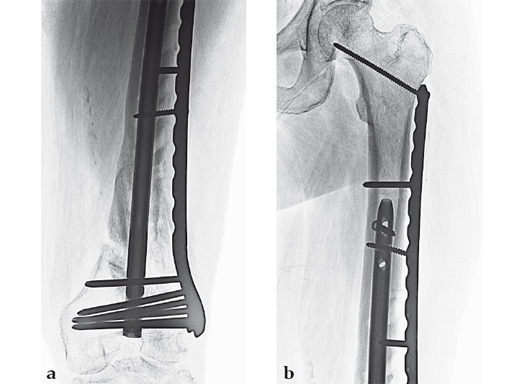

Case 3: A 53-year-old man with hypotestosteronism, low vitamin D levels, and calcium metabolism problems. Recalcitrant atrophic nonunion of his distal femur after three surgical attempts with an extension and flexion contracture of his knee.

The VA-LCP Curved Condylar Plate was used to avoid previous enlarged screw holes and allow for stable fixation in the patient's osteoporotic distal segment. Secondary to his metabolic and mechanical problems, the decision was made to proceed with an endosteal implant and place interlocking screws through that implant from the VA-LCP Curved Condylar Plate. The combination of the retrograde/antegrade femoral nail and VA-LCP provides a very stable mechanical environment for the expected prolonged healing response.